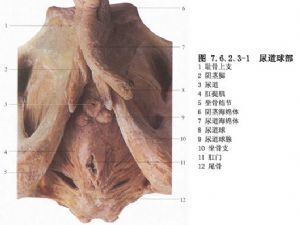

男性尿道狹窄是泌尿外科常見病,按其病因可分爲先天性、炎症性和外傷性3類。先天性尿道狹窄較少見,如先天性尿道外口狹窄、尿道瓣膜、精阜肥大、尿道管腔縮窄等。炎症性尿道狹窄由特異性或非特異性尿道感染所致。特異性感染中,以淋病性尿道狹窄較常見;非特異性感染中,因反覆包皮、陰莖頭炎症所致的尿道外口及陰莖部尿道狹窄常見,因留置導尿管不當所致的炎症性尿道狹窄已引起廣泛重視,這類狹窄多見於海綿體部尿道,範圍較廣;外傷性尿道狹窄(traumatic urethral stricture)是最常見的後天性尿道狹窄,狹窄部位依損傷部位而定,會陰跨騎傷所致者多在球部尿道。骨盆骨折所致者,位於膜部或前列腺尖端尿道,一般狹窄段不長,但瘢痕較堅硬(圖7.6.2.3-0-1~7.6.2.3-0-3)。